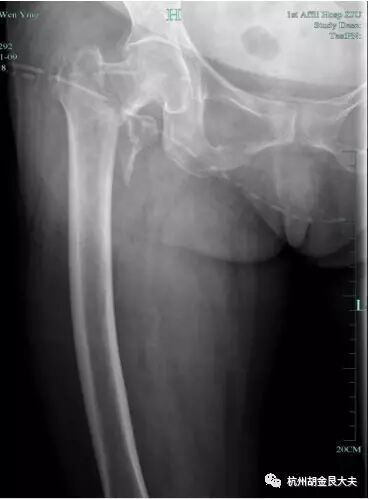

患者外伤后右髋部疼痛,摄片如下:

请给出诊断:

卷1

选择题:1.D 2.B 3.B 4.C 5.E 6.D 7.C 8.C 9.C 10.B 11.A 12.B

阅片题:

项目 | 评分标准(请酌情打√) | √ | 分值 |

读片 | 右侧 | 2 | |

股骨粗隆间骨折(或写转子间骨折) | 8 | ||

总分 10 | |||